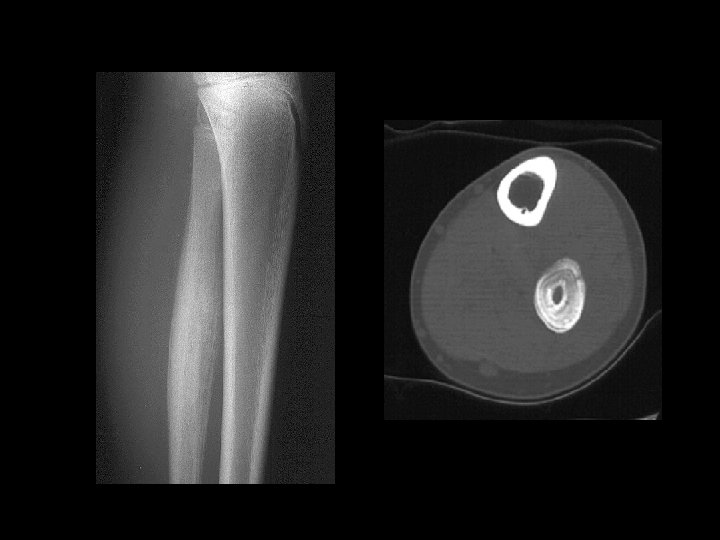

Example 10

Example 10

Example 10

Example 10